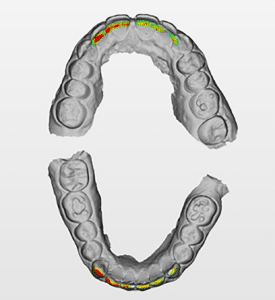

Lors de cette première consultation, en plus de l’examen clinique, on réalise une empreinte optique (Fig.2).

Fig.2.

Elle a deux buts. Le premier relève de la communication : il est plus facile pour la patiente de se rendre compte de l’état d’usure de ses dents avec une image 3D en plus des photographies et du miroir de courtoisie. Le deuxième but est l’analyse de l’occlusion. Grâce au logiciel d’exploitation (ici, Dexis IS Scan Flow), on se rend bien compte que l’occlusion est serrée avec des contacts extrêmement forts à droite (en rouge sur le Scan Flow). Il est alors facile de conclure et d’expliquer dès à présent à la patiente qu’il est impossible de restaurer son sourire dans cette situation occlusale. Pour redonner de la hauteur aux dents antérieures il faut de la place, créée soit par soustraction en préparant les dents antérieures, soit par addition en relevant la hauteur des dents postérieures. La patiente fait rapidement son choix. Pour nous, cela signifie qu’il va falloir augmenter la DVO.